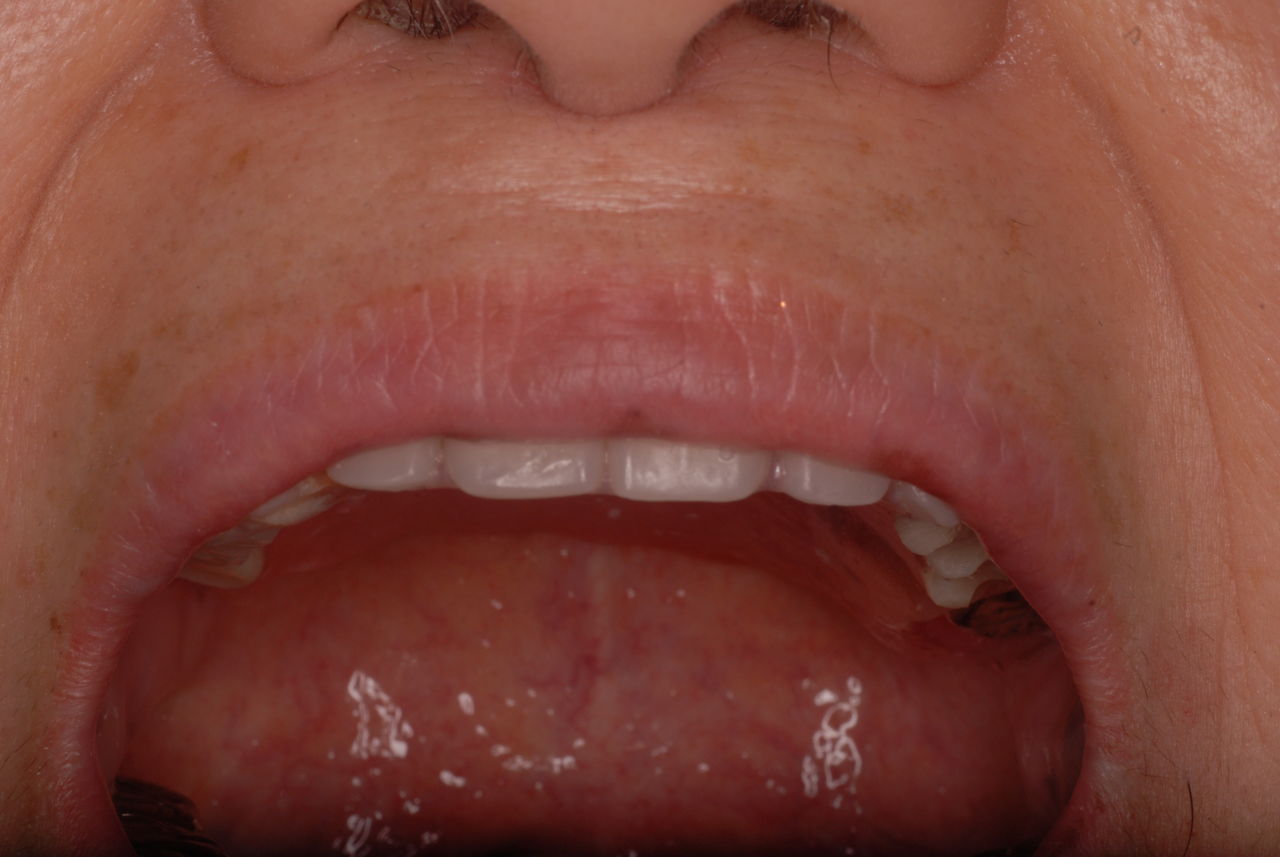

現在妊娠中で経過観察も中止。来院されたのはセラミックが取れたからでしたが、崩壊が激しく抜歯しかないような状態でした。それよりすべての歯は重症の歯周病に罹患していておそらく全ての歯は数年で抜け落ち、総義歯(総入れ歯)しかないと判断されたかたです。(そうはさせたくないのですが、本人は自覚していません。)

凄く綺麗で色白の方ですが、芸能界の方にも似て、早く綺麗にする為に歯を殺しすぐ綺麗な歯を入れるという美容的な歯科で施術したようです。

写真は殆ど崩壊し抜けたセラミックとその後修復してまだ経過監査中の歯の状態です。奥の歯は、重症の歯周病で注射もせずに抜いた歯です。